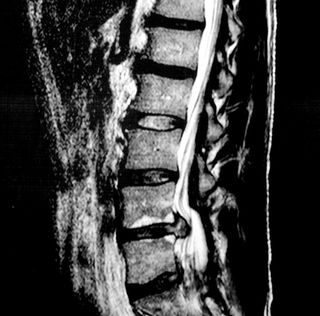

Less invasive non-surgical and surgical procedures have not corrected my husband’s protruding disks or lessened the intense pain he’s been suffering. He will be having spinal fusion surgery next week. We hope this brings permanent relief after years of back pain and, recently, loss of mobility.